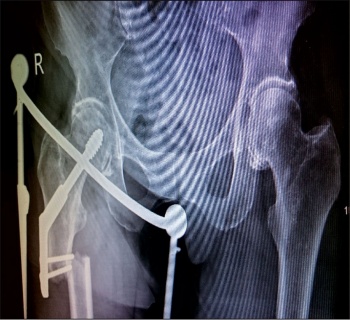

She was undergoing this treatment when in April 2015 she again had a low energy fall and was brought to hospital with pain right thigh and non-weight bearing. On x-ray she had DHS implant failure. She had the non-union of the original sub trochanteric fracture.

She was taken to theatre again and the DHS implant was removed. A long cephalomedullary nail was inserted. After that she was again started on physiotherapy.

The patient is being followed up in outpatients on a regular basis with check x-rays. She is now walking with a walking frame and is also on teriparatide injections.